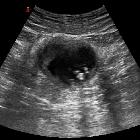

Dropped gallstones may have the following appearances on CT :

- initially calcified stones may appear as one or multiple hyperdense foci in Morrison's pouch, the gallbladder fossa and the pelvis

- cholesterol or pigmented stones may be more difficult to appreciate

- local abscess or fistula formation may also be evident in some cases